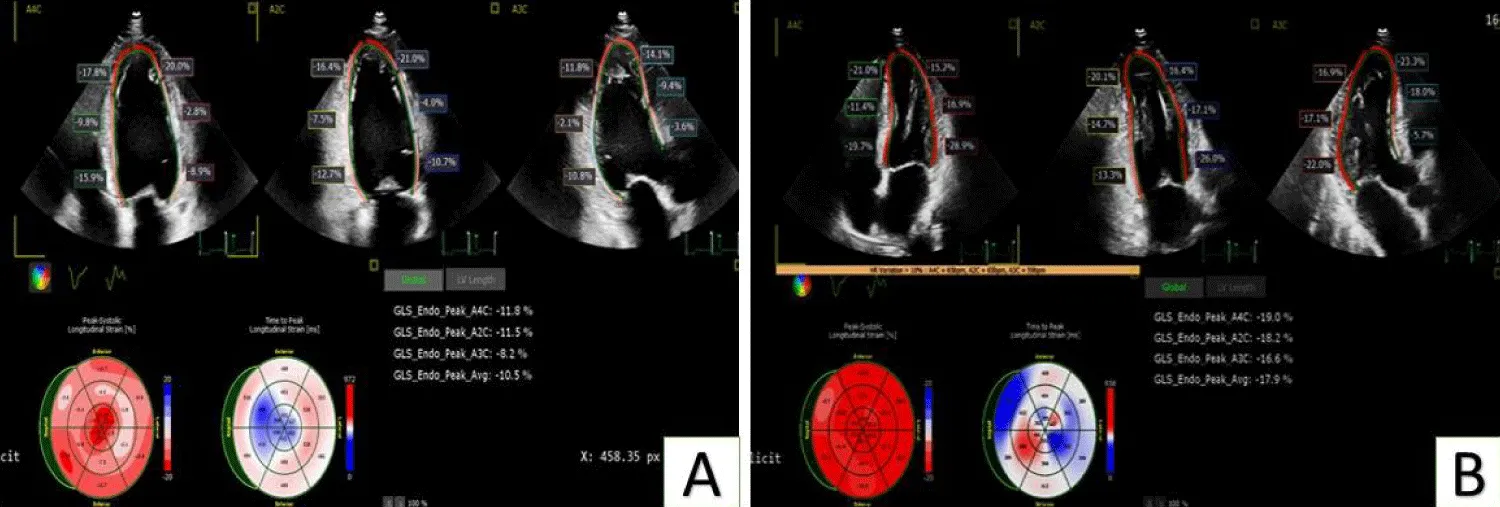

Regarding the GLS of the LV, it showed a significant increase at follow-up compared to before interventions (p < 0.001), as shown in Table 3 and Figure 1.

Figure 1: Shows the significant improvement of segmental strain and GLS of a case undergoing PCI to CTO of LCX artery. Image A: before PCI, image B: 3 months post PCI.